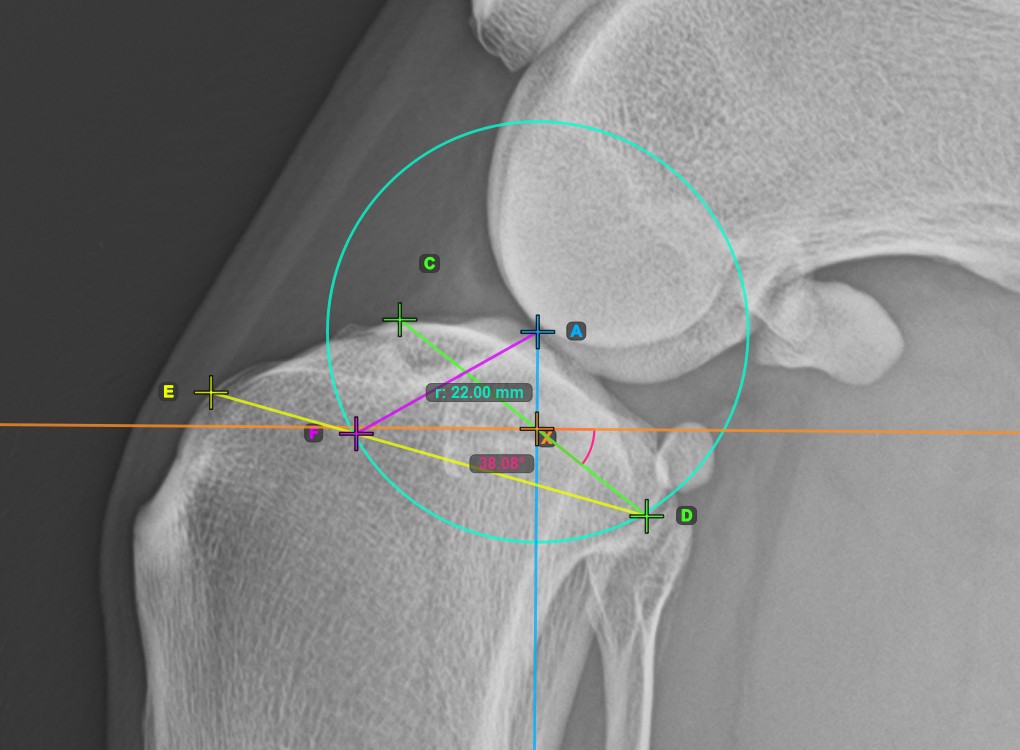

Start the TPLO extension by marking the tibial crest. The sawblade size for the TPLO extension is automatically calculated as the distance between the Eminentia Intercondylaris and the point located two thirds along the line connecting the most caudal point of the tibial head and the tibial crest.

The image below depicts the usual placement of the tibial crest point on the tibial head.